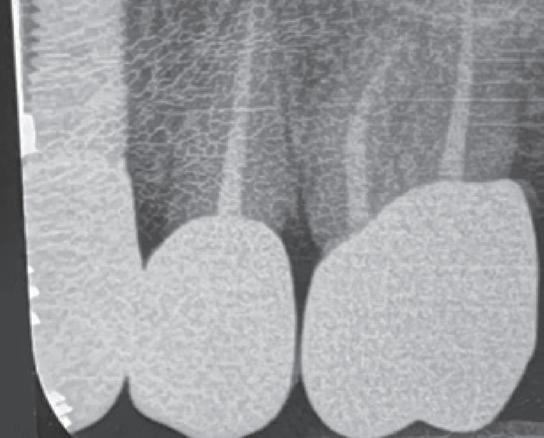

The standardisation of treatment procedures has resulted in less emphasis on craftmanship. I have quite a few gold restorations in my own mouth, two of which were placed there by a very fine dentist in 1968, both are still intact with no breakdown around the margins and both the teeth are functioning well, despite one of them having been root treated with silver points at the time. I take regular radiographs and there are absolutely no problems. I placed a number of gold restorations in my wife’s mouth before we were married in 1973 and they, too, are all still functioning well. And yet my laboratory, which

employs more than 30 technicians, has only one person who is still capable of producing good metal margins and despite all the emphasis on digital restorations and aesthetics, the dentists that I treat as patients prefer gold in their own mouths and for their families wherever possible.

In 1975, one of my patients who was 18 years old became involved in a car accident; he hit the steering wheel with his chin and sustained 2 horizontal fractures in his 31, both quite a way subgingivally. The 41 and 32 were intact. The normal treatment at that time would have required extraction of the 31 and the placement of a partial denture or a bridge to replace the missing tooth.

Knowing that he had nothing to lose, he agreed to let me experiment on him. I extirpated the 31, drilled 10mm past the apex using a sterile Kurer Post spiral drill that matched the diameter of my titanium wire. I sterilised the Titanium using a

dry heat furnace, cut it to length less some 5 mm, coated it in endodontic sealer 10 mm short of the end to make sure that I didn’t extrude sealer past the apex, tapped it into place using my implant hammer and a Unitek pin placement tool and then using G.P. points, I sealed the tapering part of the root canal. I placed an amalgam seal on the lingual. The tooth became discoloured, the patient got married and moved to Queensland. I lost contact with him in the late 70s.

Fifteen years ago, I had to refer an elderly patient to an Oral Surgeon to have some teeth removed. We got a phone call at the surgery from her daughter who wanted to understand what was happening. I called back what was a Queensland number and identified myself to the man who answered the phone. On hearing my name, he identified himself and asked whether I remembered him. Of course I did. I asked him whatever happened to that tooth. He said that it didn’t cause any problems but that it had turned jet black and he and his wife got sick of looking at it. He’d had it extracted some 5 years earlier and it was replaced by a conventional implant. I asked him about the teeth either side of it and he said that they were still there and perfectly OK.